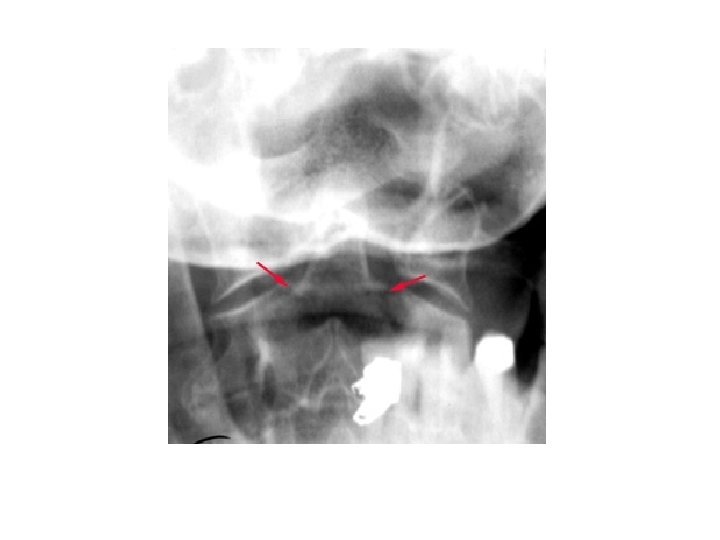

• Open mouth view • Adequate if entire Odontoid and lateral borders of C 1 and C 2 visible • Check : • lateral masses of C 1 must align with Odontoid • bilateral symmetry • Important also for Odontoid fractures